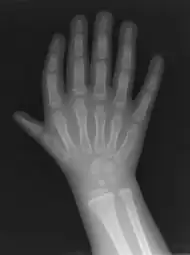

Triphalangeal thumb (TPT) is a congenital malformation where the thumb has three phalanges instead of two. The extra phalangeal bone can vary in size from that of a small pebble to a size comparable to the phalanges in non-thumb digits. The true incidence of the condition is unknown, but is estimated at 1:25,000 live births.[1] In about two-thirds of the patients with triphalangeal thumbs, there is a hereditary component.[2] Besides the three phalanges, there can also be other malformations. It was first described by Columbi in 1559.[3]

The triphalangeal thumb has a different appearance than normal thumbs. The appearance can differ widely; the thumb can be a longer thumb, it can be deviated in the radio-ulnar plane (clinodactyly), or thumb strength can be diminished. In the case of a five-fingered hand it has a finger-like appearance, with the position in the plane of the four fingers, thenar muscle deficiency, and additional length. The flexion and extension can be limited as well.[4]There is often a combination with radial polydactyly.

The diagnosis can be made on a physical examination and on an X-ray.[4]